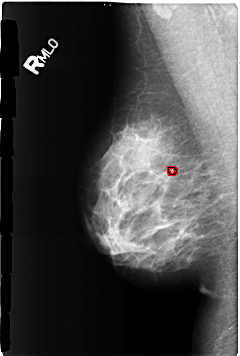

B_3169_1.RIGHT_MLO

RIGHT_MLO LINES 4624 PIXELS_PER_LINE 3112 BITS_PER_PIXEL 12 RESOLUTION 50 OVERLAY

FILE: B_3169_1.RIGHT_MLO.OVERLAY

TOTAL_ABNORMALITIES 1

ABNORMALITY 1

LESION_TYPE CALCIFICATION TYPE LUCENT_CENTER DISTRIBUTION N/A

ASSESSMENT 2

SUBTLETY 3

PATHOLOGY BENIGN_WITHOUT_CALLBACK

TOTAL_OUTLINES 1

BOUNDARY